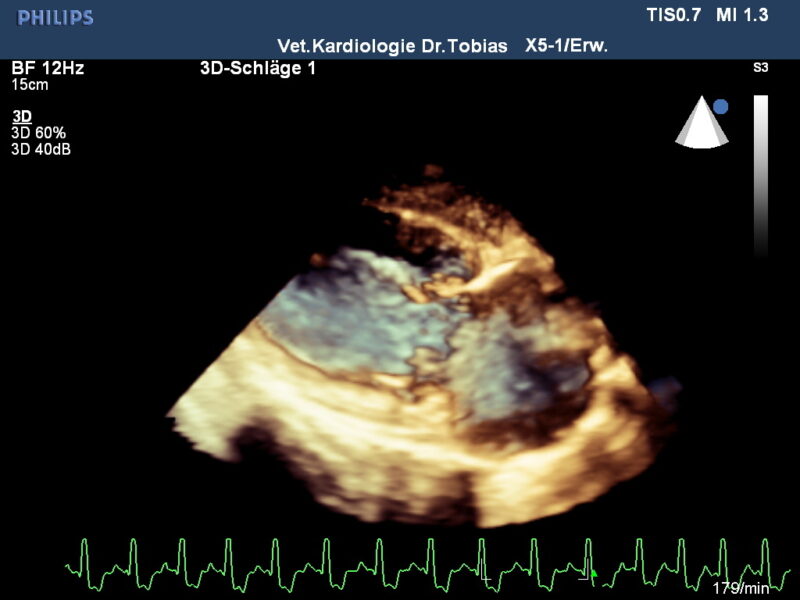

In der kardiologischen Diagnostik sind wir interessiert, diese Fälle so früh wie möglich zu ermitteln, um rechtzeitig ab gewissen Schweregraden therapeutisch sinnvoll gegensteuern zu können. Viele dieser Patienten gelten bei Hundebesitzern noch als asymptomatisch. Neben dem Vorbericht nutzen wir die klinische Untersuchung, das EKG, die bildgebende Diagnostik (radiologischen Thorax Untersuchung sowie eine standardisierte Echokardiographie mit ein- und zweidimensionalem Echo, sowie der Doppleruntersuchung). Spezialisten wenden auch 3D- und 4 D-Techniken an, die insbesondere bei Jetquantifizierung Vorteile haben. Zusätzlich werden Laboruntersuchungen genutzt, die kardiale Biomarker wie NTproBNP und sensitives Troponin I enthalten können.

Der Autor arbeitet mit dem Phillips-System, welches eine semi-automatische Cardiac-Motion-Quantifizierung (aCMQ) vornimmt. Der Anwender wählt in der Region Of Interest drei Punkte an: im Bereich des Mitralklappenanulus jeweils einen und den dritten in der Herzspitze. Das System erkennt die kardialen Grenzlinien und nimmt Abstand zum Epikard. Speckles repräsentieren Gewebemarker, die in den Grauskalen des Herzechos im zweidimensionalen Bild verteilt sind und durch den Herzzyklus Bild für Bild verfolgt werden (Tracking). Das Speckle Tracking ist in der Lage verschiedene Eben zu erfassen: longitudinale, radiale und circumferentiale.